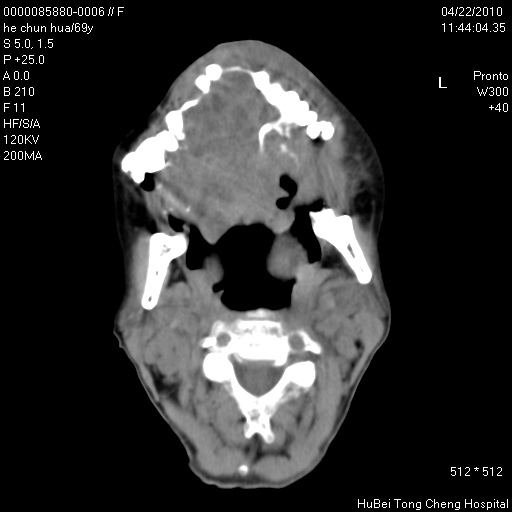

标题: CT25937:女,69Y

硬腭部包块十余年,渐进性增大。